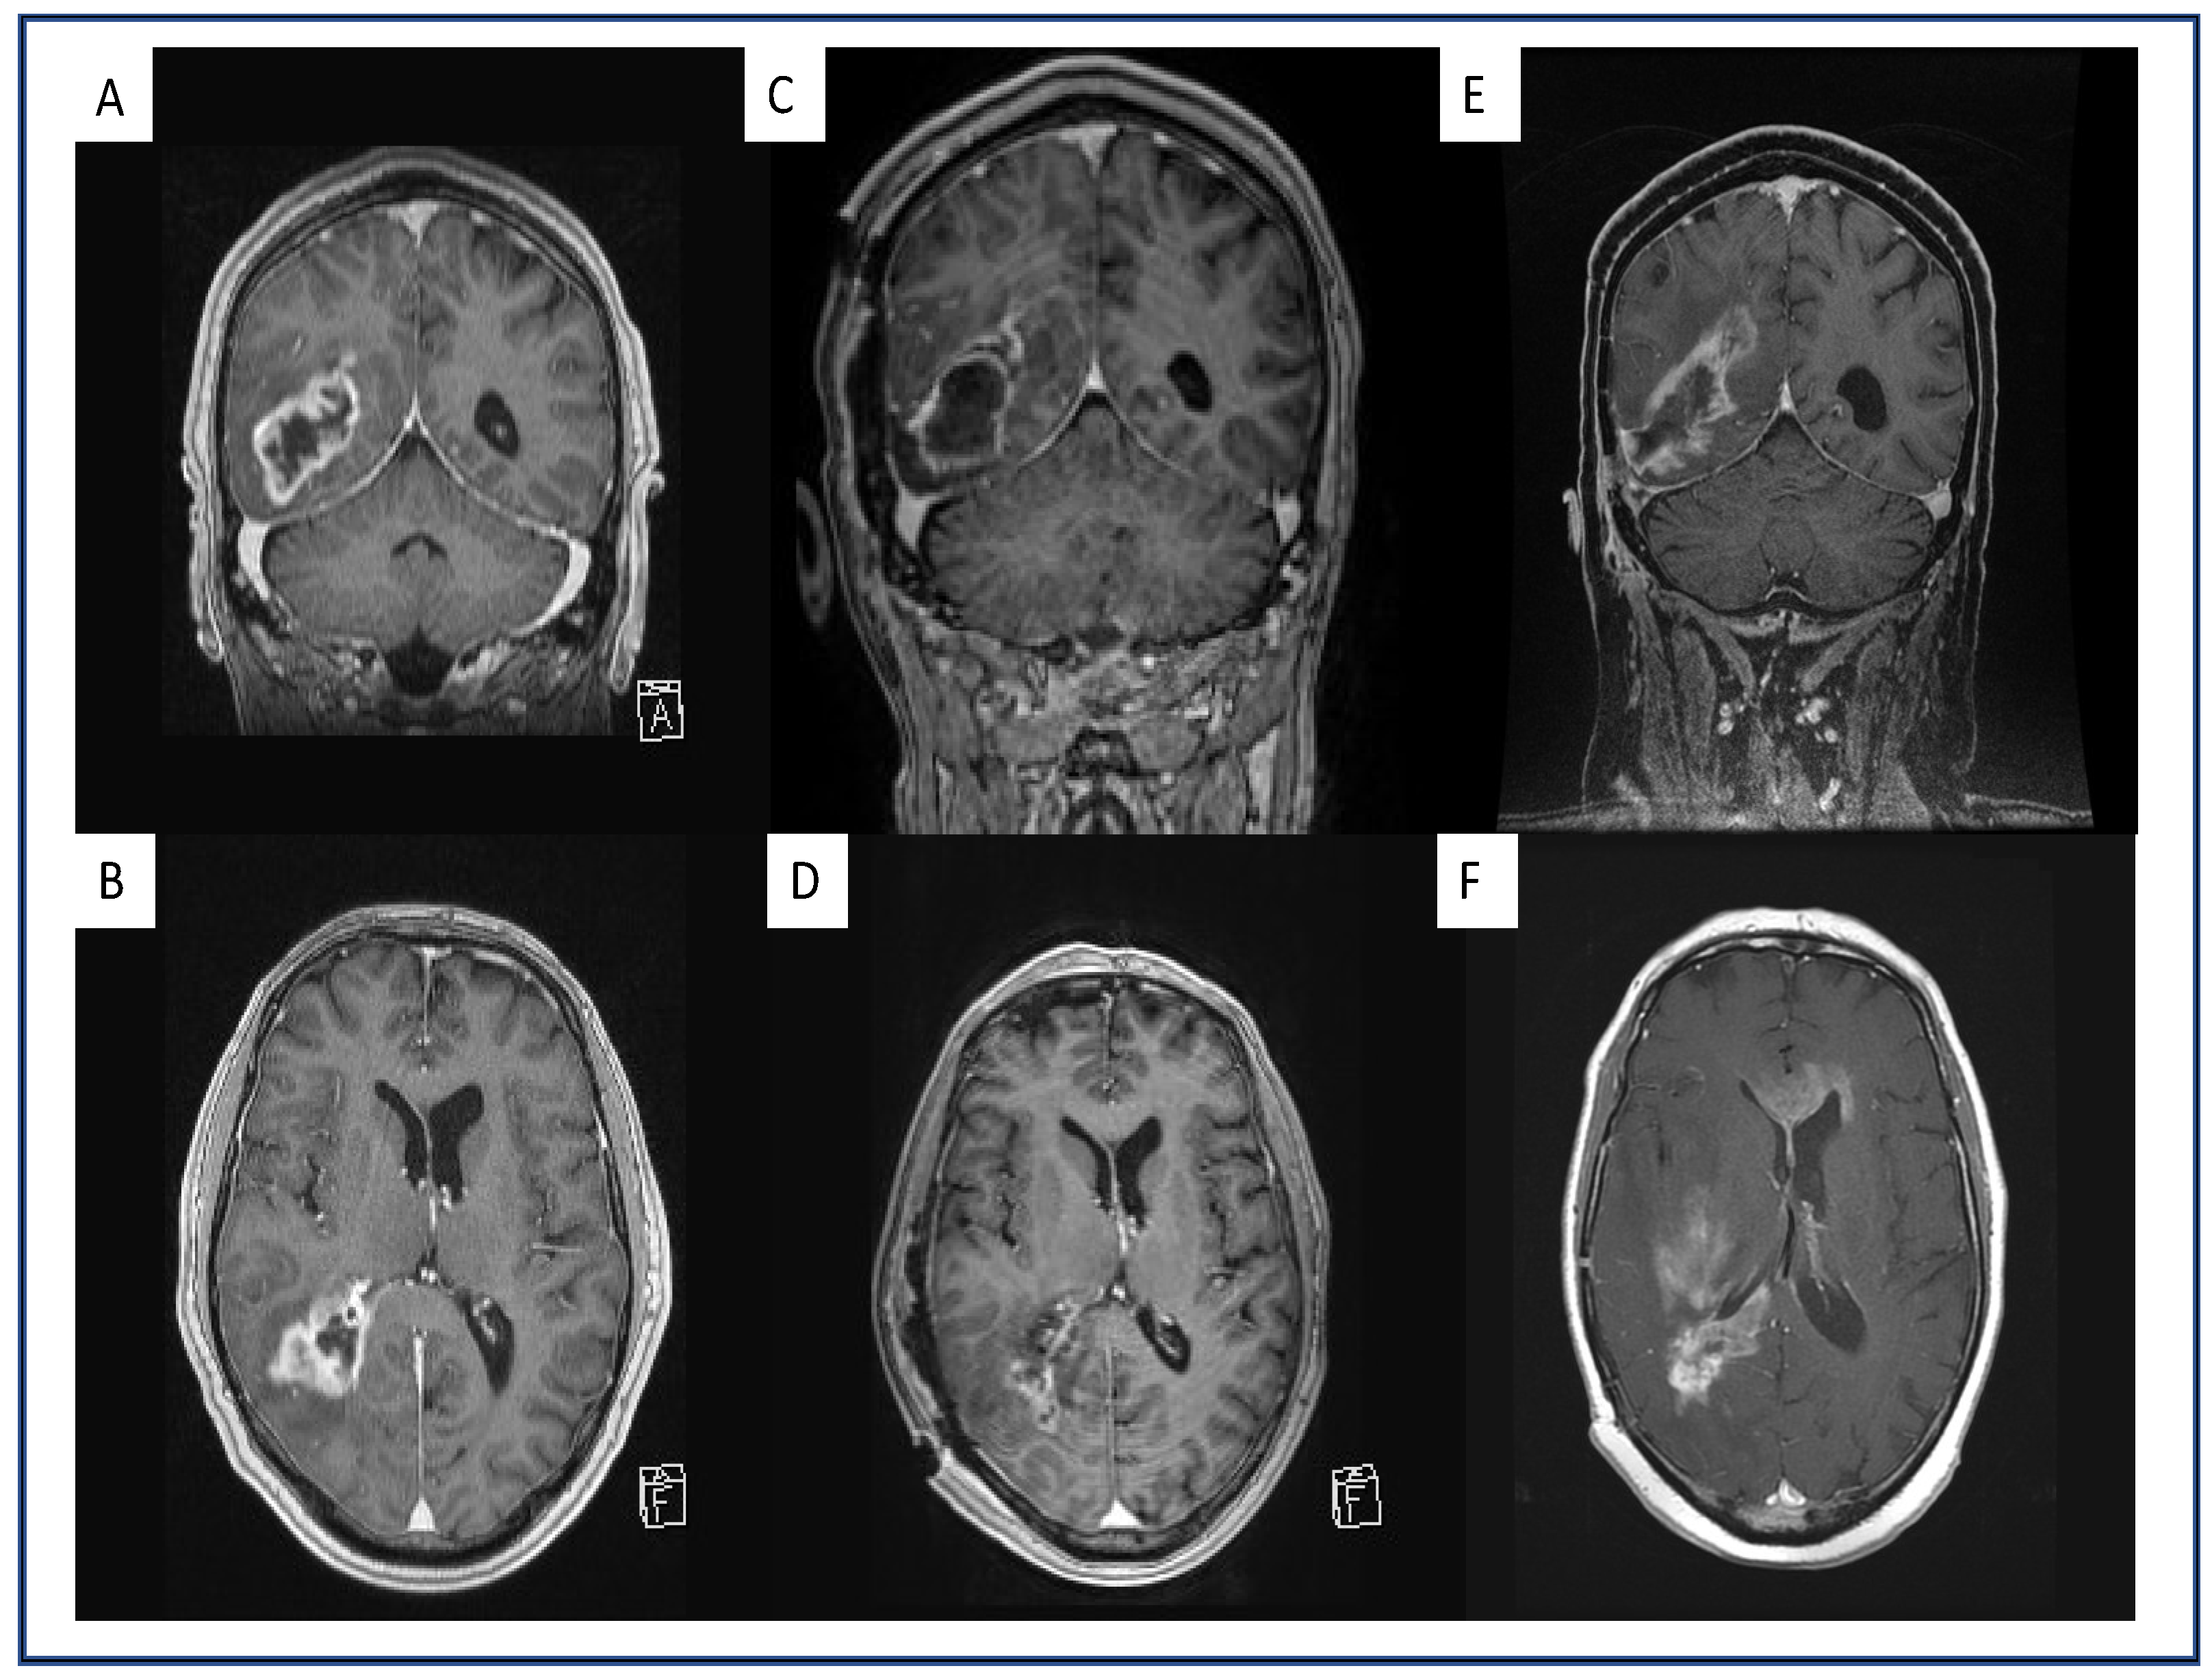

4.1. Multifocal and Midline-Crossing Relapse

4.2. Sharp Demarcated Lesions

4.3. Analysis of Intratumoral Hemorrhage